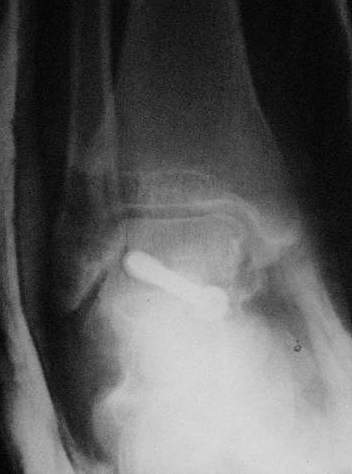

При лечении переломов шейки таранной кости очень важно увидеть вторую проекцию шейки, только боковой проекции недостаточно.

В приложении укладка Канале.